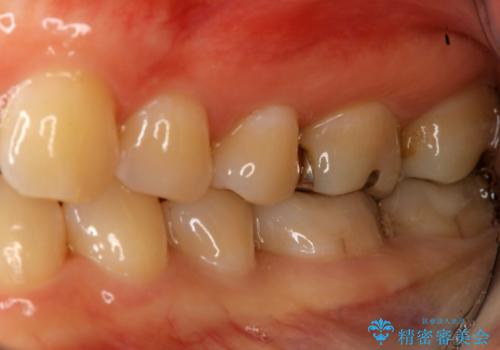

下の奥歯の銀歯を白くしたい

- 左下奥歯のメタルインレーを白くしたいと希望された患者様です。

形態、切削量などを考慮し、セラミックインレーにて治療を行いました。